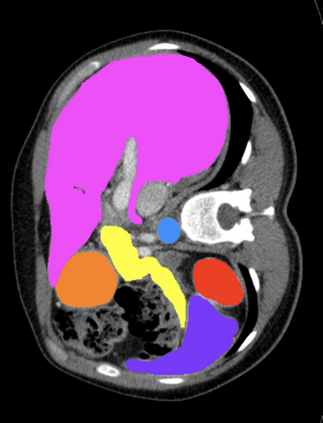

Most recent semantic segmentation methods adopt a U-Net framework with an encoder-decoder architecture. It is still challenging for U-Net with a simple skip connection scheme to model the global multi-scale context: 1) Not each skip connection setting is effective due to the issue of incompatible feature sets of encoder and decoder stage, even some skip connection negatively influence the segmentation performance; 2) The original U-Net is worse than the one without any skip connection on some datasets. Based on our findings, we propose a new segmentation framework, named UCTransNet (with a proposed CTrans module in U-Net), from the channel perspective with attention mechanism. Specifically, the CTrans module is an alternate of the U-Net skip connections, which consists of a sub-module to conduct the multi-scale Channel Cross fusion with Transformer (named CCT) and a sub-module Channel-wise Cross-Attention (named CCA) to guide the fused multi-scale channel-wise information to effectively connect to the decoder features for eliminating the ambiguity. Hence, the proposed connection consisting of the CCT and CCA is able to replace the original skip connection to solve the semantic gaps for an accurate automatic medical image segmentation. The experimental results suggest that our UCTransNet produces more precise segmentation performance and achieves consistent improvements over the state-of-the-art for semantic segmentation across different datasets and conventional architectures involving transformer or U-shaped framework. Code: https://github.com/McGregorWwww/UCTransNet.